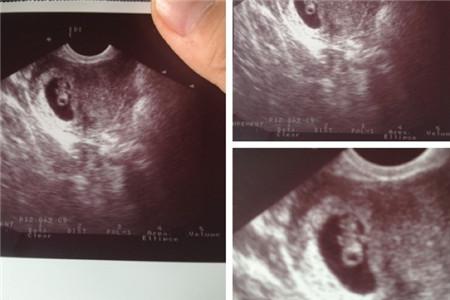

其实医生已经有过解释,输卵管造影使用的泛影脯胺或碘油并不会造成副作用,但是就算不通过造影也有自我观察的方法来达到输卵管堵塞早期发现的目的,大家可以对比以下16中症状: